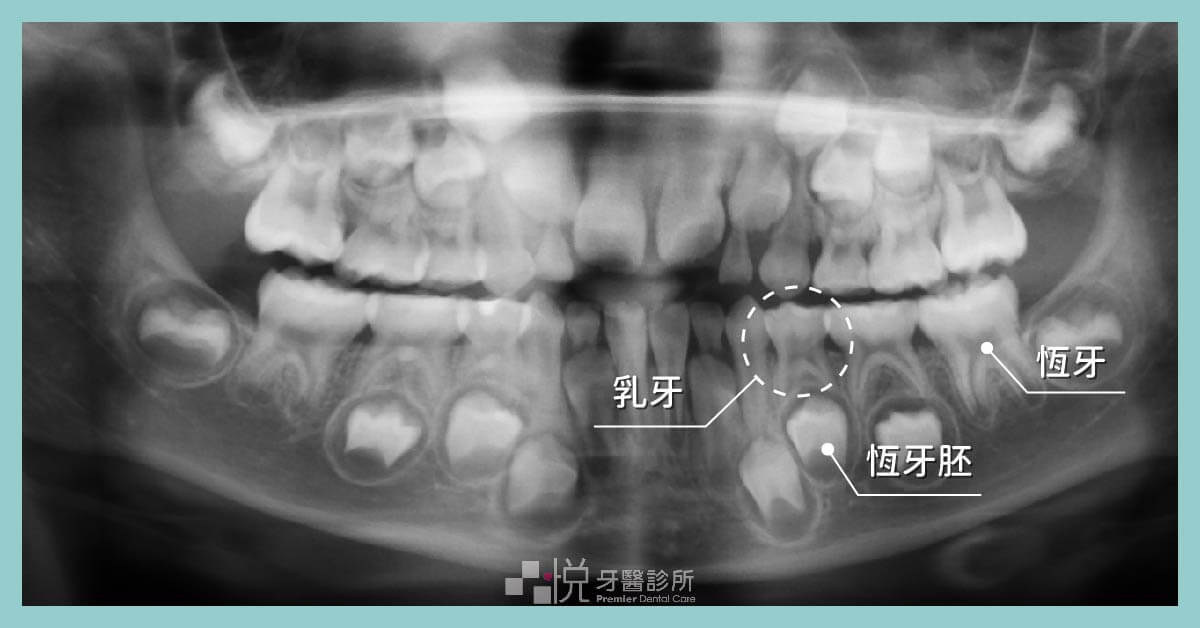

其實各位家長不用太著急,牙醫師會先照環口全景 X 光片 (Panoramic x-ray),確認有無缺牙的狀況,若無,乳牙換牙其實如同身高一般,每個人的生長年齡發育本來就不盡相同。

這代表小朋友開始要進入混和齒列階段,同時有乳牙和恆牙於口內,此時會遇到什麼狀況呢?乳牙換牙有什麼地方需要特別注意的呢?